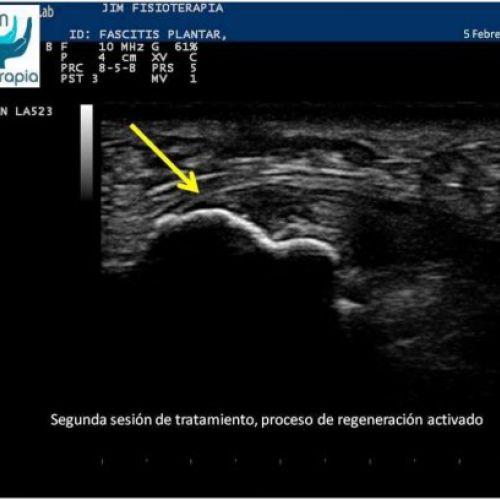

Tratamiento de fascitis plantar con EPI®

Terapia de electrólisis percutánea intratisular EPI® para el tratamiento de la fascitis plantar.